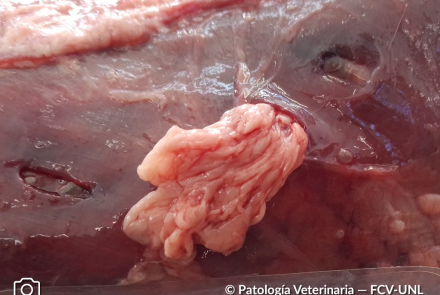

Evisceración de Omento

Sección de omento atravesando solución de continuidad de la pared abdominal, provocada por mordeduras de caninos.

Especie: Felino